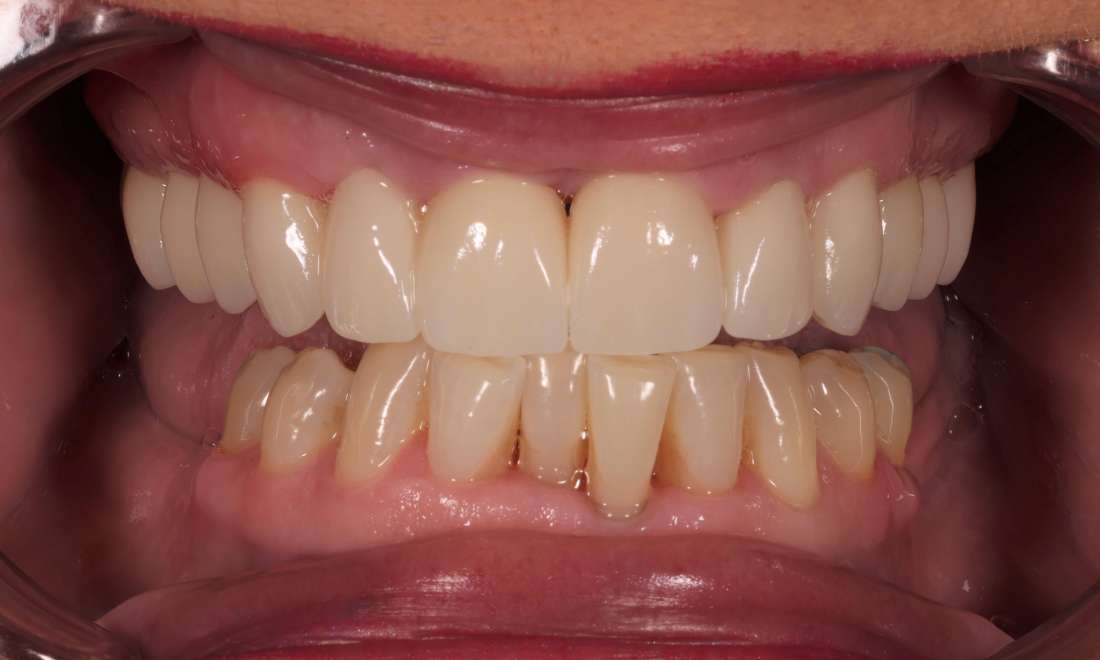

Upper Arch Reconstruction with Crowns and Bridges

Over several well-planned visits, we were able to remove hopeless teeth, complete initial gum disease treatment, complete root canals on teeth with pain and infection, and then make long term 3D printed temporary crowns and bridges to test out her newly established bite. Missing teeth on the lower arch will be replaced with dental implants in the future.

After several months of success with the 3D printed temporary crowns we made final scans of her teeth for Zirconia crowns to restore damaged teeth and Zirconia bridges to replace missing teeth. Her commitment to excellent home care with a powered toothbrush twice daily, daily flossing, and a prescription strength toothpaste has transformed her gum health. She can now smile confidently and chew comfortably.